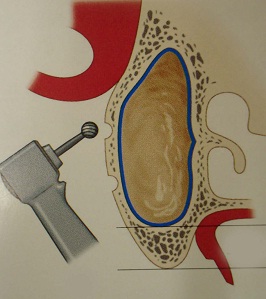

明日は久しぶりにサイナスリフトのオペが入っている。しょっちゅうあるわけではないので、オペ前には感覚を戻すために、必ず生卵で練習している。生卵で100発100中うまくいけば、臨床では100パーセントうまくいくという話もあるが、臨床の方がいろんな制約があって(出血するとか、見ずらいとか)、結構大変だ。高速回転の昔ながらの機械で、生卵の中の膜を破らずに窓開けをする。生卵の殻が実際の臨床では顎の骨に相当する。最近はピエゾサージェリーなる超音波の機械がはやってきて窓開けも楽ちんになったという話をよく聞く。今日バイトに来てたN先生に聞いたら、「医科歯科大インプラント治療部ではピエゾから昔のやり方に戻った」とのこと。やはり手の感覚に勝るものは無いのか?2002年にミシガン大学に行ってまで覚えたこの手術。患者さんごとに解剖学的構造が異なるので、ちょっと慣れたからと言って舐めてはかかれない。前の晩は妙に緊張する。さあ早く寝よう。

生卵でサイナスリフトの練習